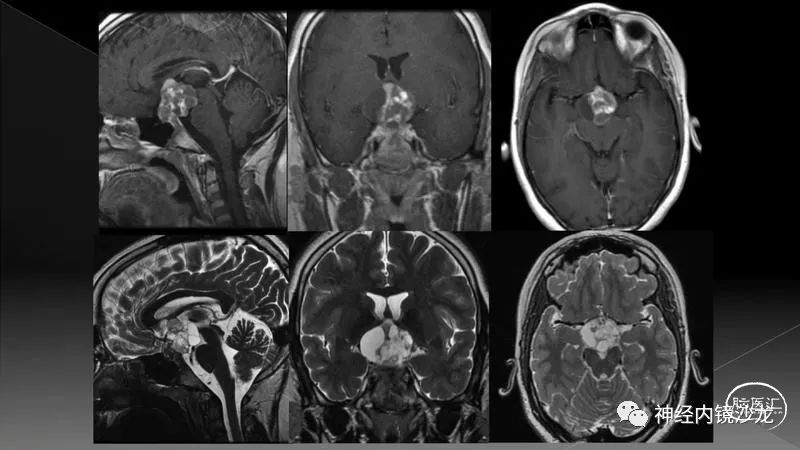

一例2岁的巨大颅咽管瘤患儿,表现为癫痫发作和全垂体功能减退。病变最初在其他机构行经额囊肿开窗术,但后来逐渐增大。我们考虑了多种治疗方案;推荐了内镜经鼻入路,以期最大程度地安全切除肿瘤。

采用虚拟现实模拟和3D打印技术来评估鼻窦气化不良和鼻腔的整体大小是否影响手术操作。我们的实验室结果表明双侧鼻腔入路可行。

手术暴露充分术野,从蝶骨平台到斜坡,从眼眶到眼眶。切除大块钙化部分肿瘤后,我们找到肿瘤包膜和下丘脑、视觉通路之间的清晰的分离平面。切除结束时,发生了后交通动脉从大脑后动脉撕脱导致的动脉出血。采用单轴持夹器放置一个成角的动脉瘤夹,以夹闭损伤部位并保证供血动脉不狭窄。术后即刻和晚期磁共振成像和CTA检查显示肿瘤全切、无卒中、无假性动脉瘤形成。